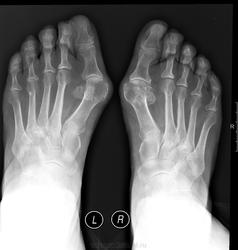

Рентген стоп. Дефект суставной поверхности основной фаланги первого пальца слева

Рентген стоп. Дефект суставной поверхности основной фаланги первого пальца слева)) может быть постртравматической природы?

какой дефект? нет дефекта, фаланги др на др проецируются...

Поддерживаю. Дефекта нет.

Нет, не дефект. Просто хорошее качество снимков. Отличные снимки, спасибо.

Тоже не вижу дефекта

Но поперечное плоскостопие с hallux valgus имеется.

+ Артроз

Да, просто неопытный взгляд что-то пытается лишнее увидеть))

Скиалогические дела. Основание ногтевой фоланги накладывается на головку основной и получается такой эффект. Пройдитесь по контуру каждой кости и всё станет ясно.

+1. Суммация теней.